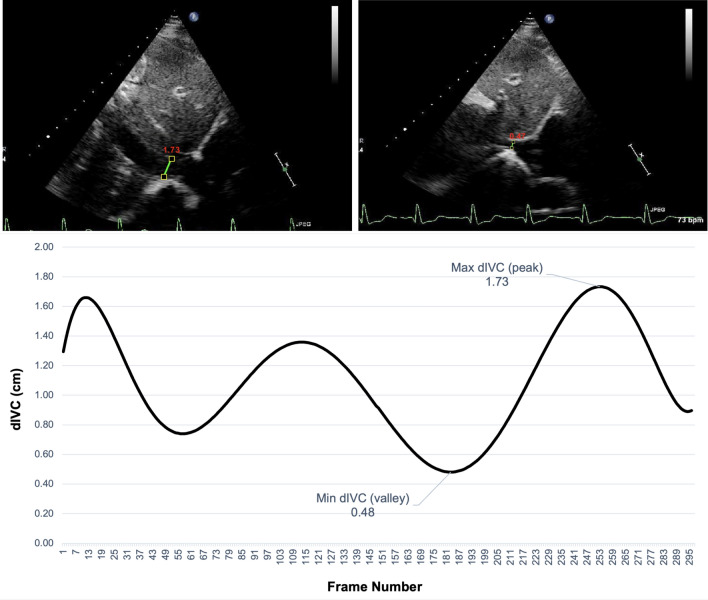

The automatically delineated region in each frame is used to derive dIVC by measuring IVC diameter 2 cm from the junction of the right atrium. As this dIVC calculation is performed in each frame, the calculation of IVCs diameter was performed over frames. Figure 4 shows an example of the absolute maximum and minimum dIVC as well as dIVC curve over frames.

Fig. 4.

Top left: automated dIVC in frame 253 of a given video with a dIVC of 1.73 cm (maximum dIVC); top right: automated dIVC in frame 183 of a given video with a dIVC of 0.475 cm (minimum dIVC); bottom: dIVC in each frame of a given clip, where the peaks indicate maximum dIVC and valleys indicate minimum dIVC